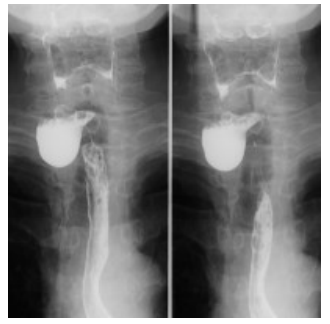

Observe a imagem a seguir.

Quanto à patologia demonstrada na imagem, assinale a alternativa correta